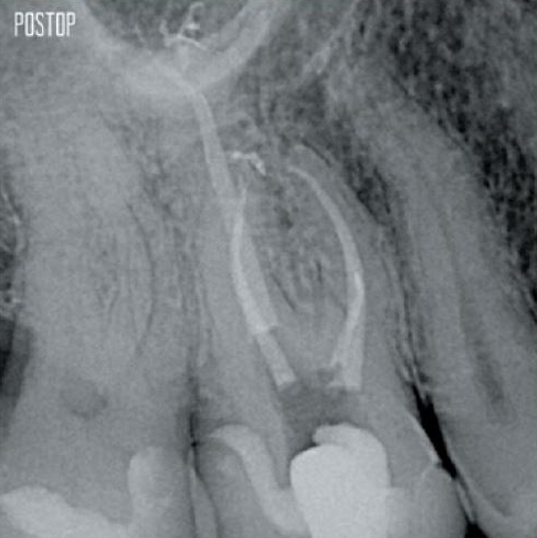

Korunan dentin sayısında artış. Uygun şekillendirme, yıkama ve obtürasyon sağlanır.

Fotoğraflar Dr. Ahmed Salman'ın izniyle kullanılmıştır